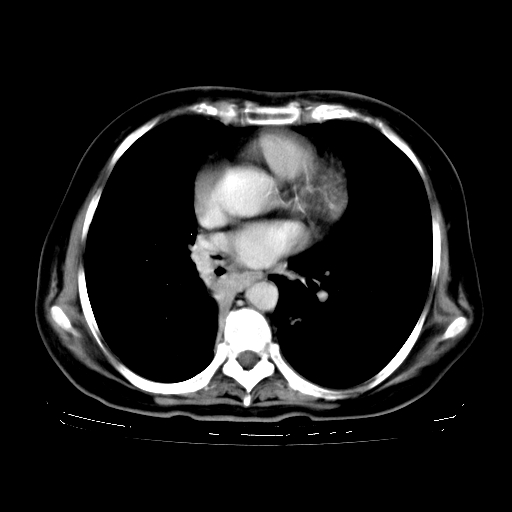

2.胸主动脉夹层。

4、主动脉夹层。

1.左上肺结核,部分纤维化。右肺中下叶部分肺不张,内见液化、坏死及点状钙化,右中下叶支气管壁增厚、管腔狭窄,见多个点状钙化,结合临床考虑支气管内膜结核,建议痰检查抗酸杆菌并参考血沉。两肺多个小圆点状高密度灶,境界模糊,多考虑结核肺内播散。但本人年龄较大首先应支气管镜检以除外右肺癌。

支持,首先一元论解释。胸主动脉部分层面环形低密度,中心强化。环形影不强化。不象真假腔的改变。我考虑动脉炎,不太支持夹层动脉瘤-和大家的观点不一致,希望楼主让患者再做个心血管的彩超吧。